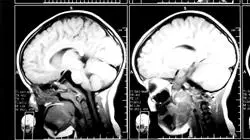

Die Überalterung der Bevölkerung macht die Prävalenz dieser Krankheiten sehr relevant. Eine angemessene Handhabung, frühzeitige Erkennung, symptomatische und ausgedehnte Behandlung sind entscheidend für die beste Prognose.

In diesem universitätskurs werden Sie die grundlegenden Aspekte für die Verwaltung desselben kennenlernen. Von der Differentialdiagnose über die angemessene Behandlung in jedem Fall bis hin zur Erkennung ataktischer Syndrome im Gegensatz zu anderen Syndromen.

Zu diesem Zweck wird die Erkennung von frühen Anzeichen und Symptomen bei diesen Erkrankungen eingehend erörtert, einschließlich der Untersuchung der genetischen Grundlagen der neurodegenerativen Ataxien.